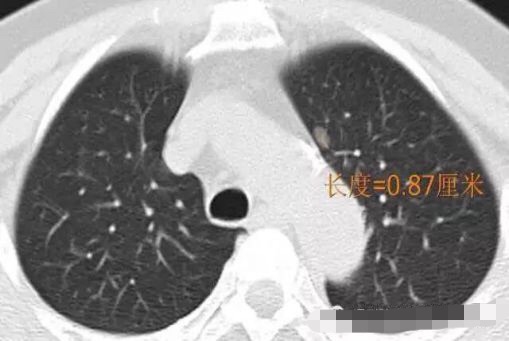

2014年 首次发现右肺上叶GGO,病灶直径8.3毫米, 2016年复查发现右肺上叶GGO,病灶直径12.4毫米。2年大约生长4毫米,平均1年生长2毫米。2016年手术病理结果:浸润性腺癌。

2016年病灶直径12.4毫米